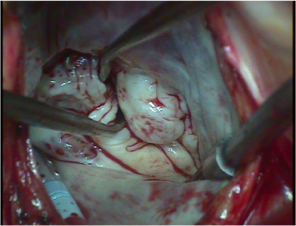

狭心症や心筋梗塞といった冠動脈の動脈硬化性病変に対する手術を冠動脈バイパス術といいます。現在でも多くの施設では人工心肺装置(図2)という大きな機械を心臓に装着してこの手術を行っていますが、機械による非生理的な血流であるため、脳血管の狭窄が強い患者さんや、腎機能障害や呼吸機能障害を有する重症の患者さんは合併病変が悪化することが危惧されていました。この問題を解決すべく、当院では2000年から人工心肺装置を用いずに、スタビライザー(図3)と言う器具を、冠動脈の走行する心臓表面に固定して拍動を抑えて血管縫合する<心拍動下冠動脈バイパス術>を導入しました。単独冠動脈バイパス手術の95%以上で行っております。

図1:心拍動下冠動脈バイパス術